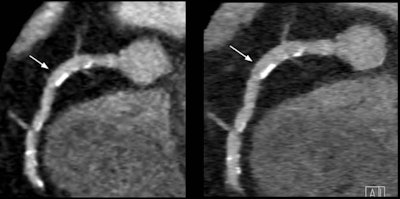

Use of the IC detector in coronary CT angiography yielded higher image quality in patients, both with (right) and without (left) the use of iterative reconstruction."With filtered back projection and the conventional detector at the 60% stenosis, it seems like it almost no lumen left, but when you go to the integrated detector you can see the effect, which becomes really apparent when you look at the combination of the thinner slice thickness, iterative reconstruction, and the new detector, where you can still discern the lumen at 60% stenosis," he said, and the difference is also visibly apparent at the 50% stenosis level.

Phantom coronary CT angiography images with a slice thickness of 0.5 mm reconstructed with iterative reconstruction obtained by the integrated circuit detector improved measurement accuracy by the greatest degree. A 60% stenosis at filtered back projection appears to occupy the entire lumen, with the conventional detector, while demonstrating nonstenosed lumen using the new detector and even more with the addition of iterative reconstruction. All images courtesy of Dr. Fabian Morsbach.The patient arm also showed significantly (p < 0.001) higher image quality -- and stenoses were quantified as significantly smaller using iterative reconstruction: 47.6% versus 42.1% (mean difference 5.5%, p = 0.009).